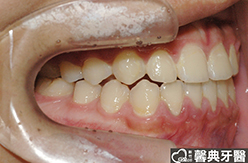

上、下顎前突,俗稱暴牙,由於上下前牙向前暴出,在外觀上容易產生牙齒外露的現象,雙唇較難自然閉合,嘴唇看也來也會比較厚。

患者︰趙同學,20多歲,學生。

主訴︰齒列不正,暴牙,不好看。

治療計劃︰上下顎齒列平整、後縮,重建正常咬合關係。

| ●治療前 | ●治療後 | |